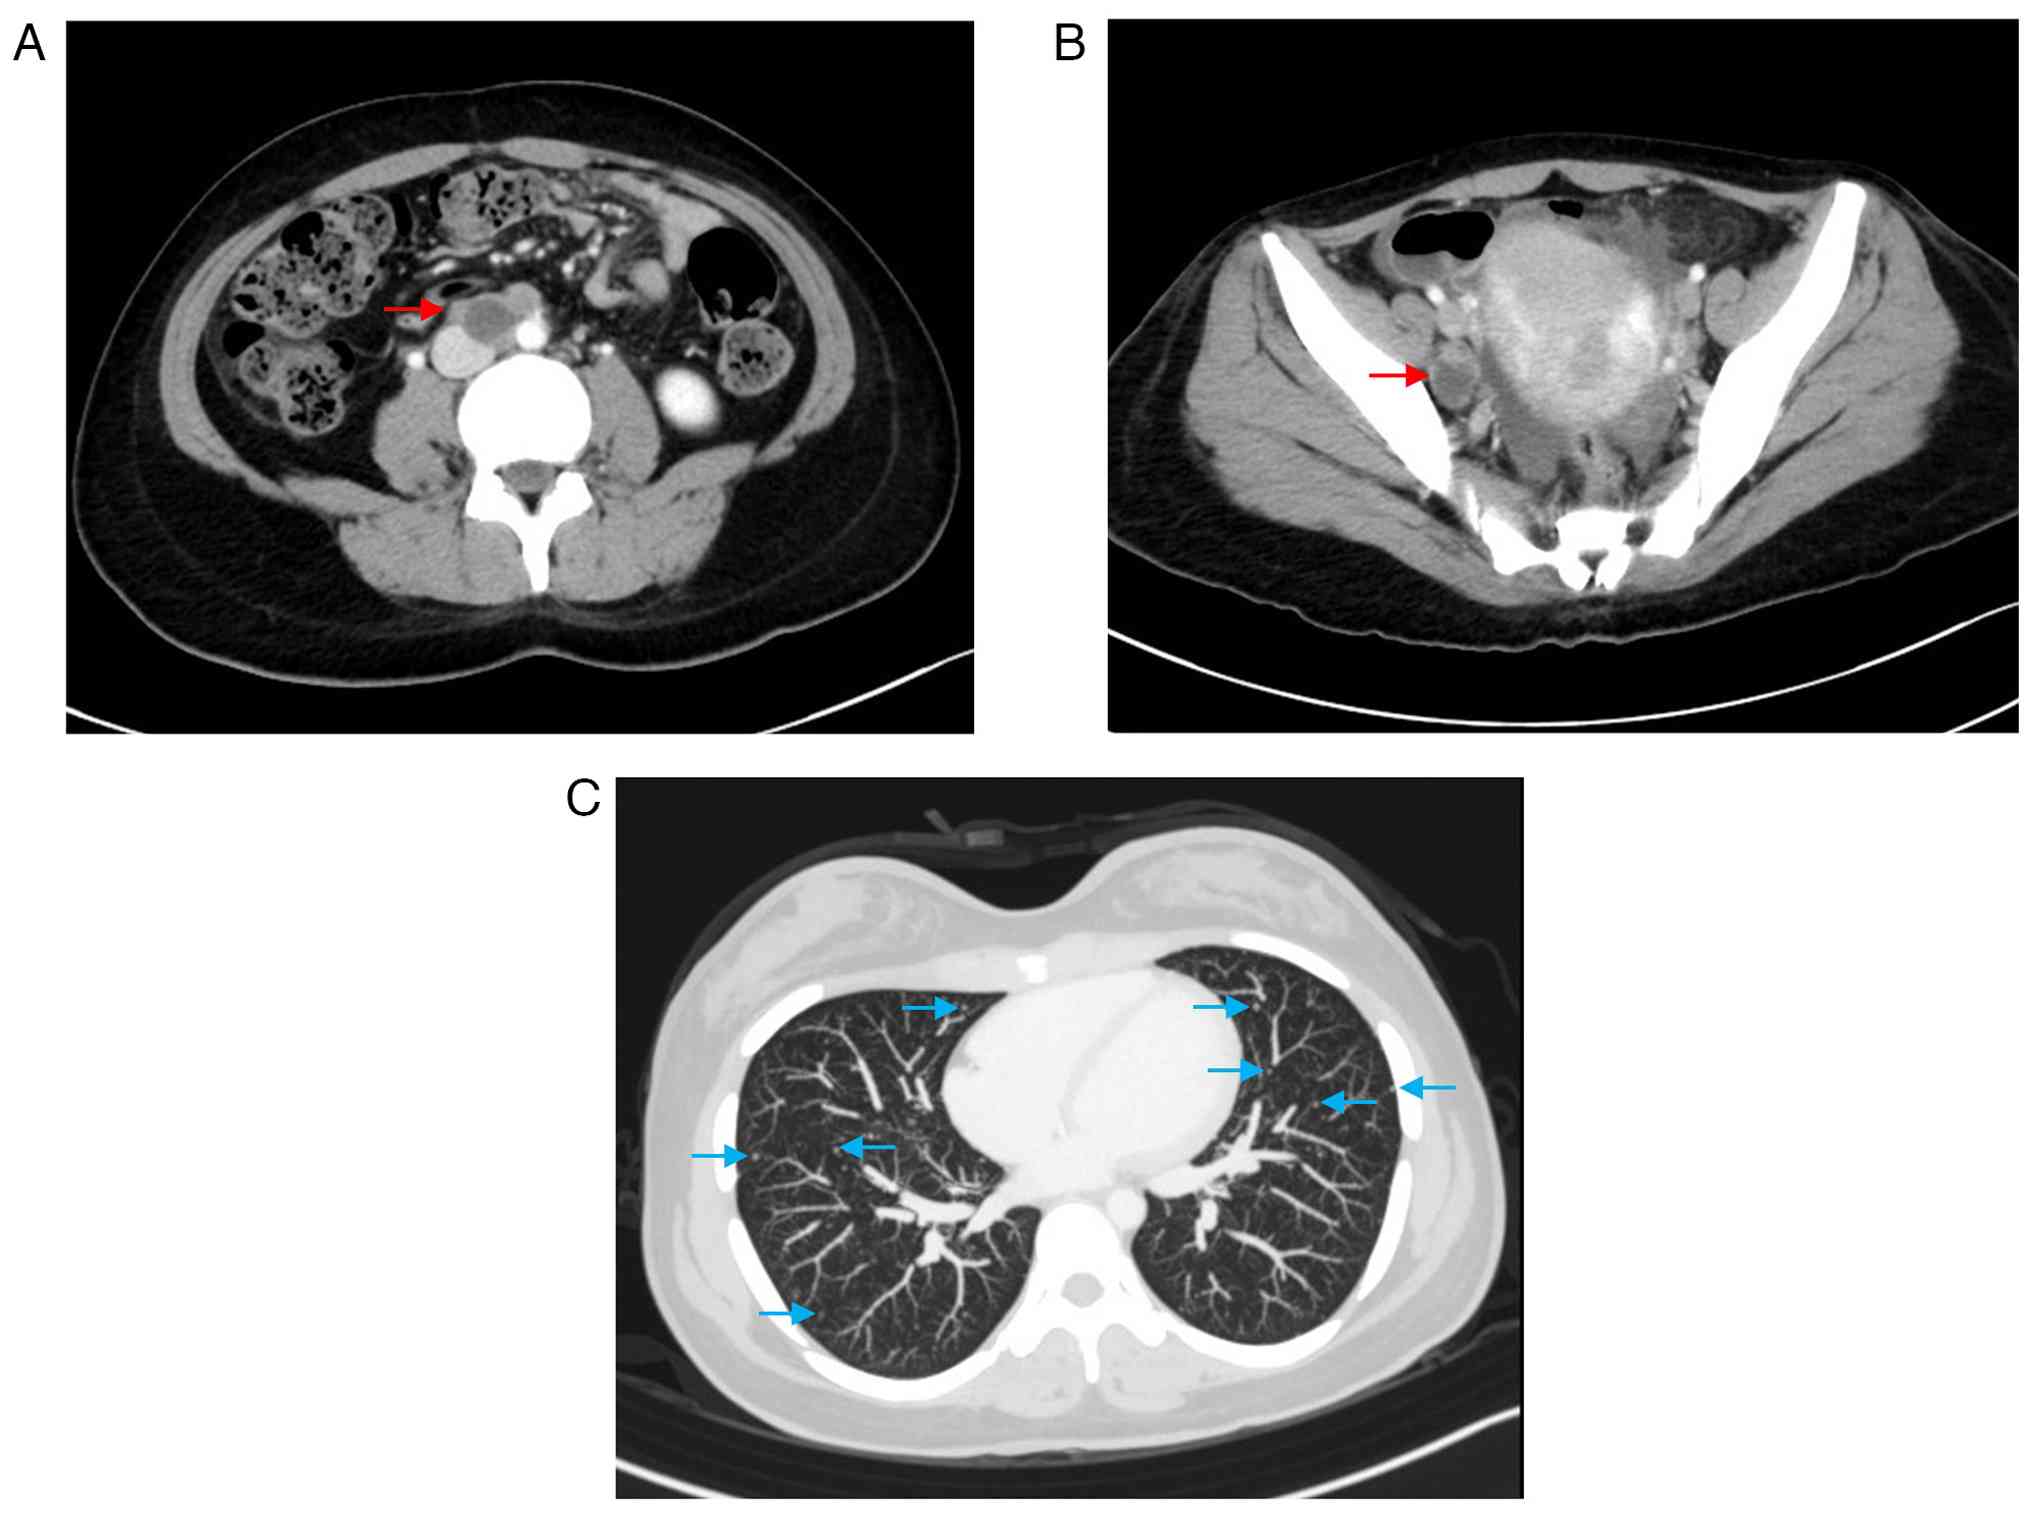

The patient was treated with four cycles of paclitaxel and carboplatin chemotherapy. Subsequently, durvalumab and olaparib were approved for reimbursement under the Japanese national health insurance system for the treatments of endometrial cancer. Therefore, the patient received an additional four cycles of combination chemotherapy with paclitaxel, carboplatin, and durvalumab. Post-chemotherapy CT showed a complete response according to RECIST criteria (Fig. 5A-C). Immunohistochemistry confirmed mismatch repair, and maintenance therapy with durvalumab and olaparib was initiated. The patient has remained progression-free for 10 months.

Treatment response on computed

tomography. (A) Resolution of the previously enlarged para-aortic

lymph nodes. (B) Resolution of the previously enlarged pelvic lymph

nodes. (C) Disappearance of multiple pulmonary nodules. These

findings were consistent with a complete response.

Treatment response on computed tomography. (A) Resolution of the previously enlarged para-aortic lymph nodes. (B) Resolution of the previously enlarged pelvic lymph nodes. (C) Disappearance of multiple pulmonary nodules. These findings were consistent with a complete response.